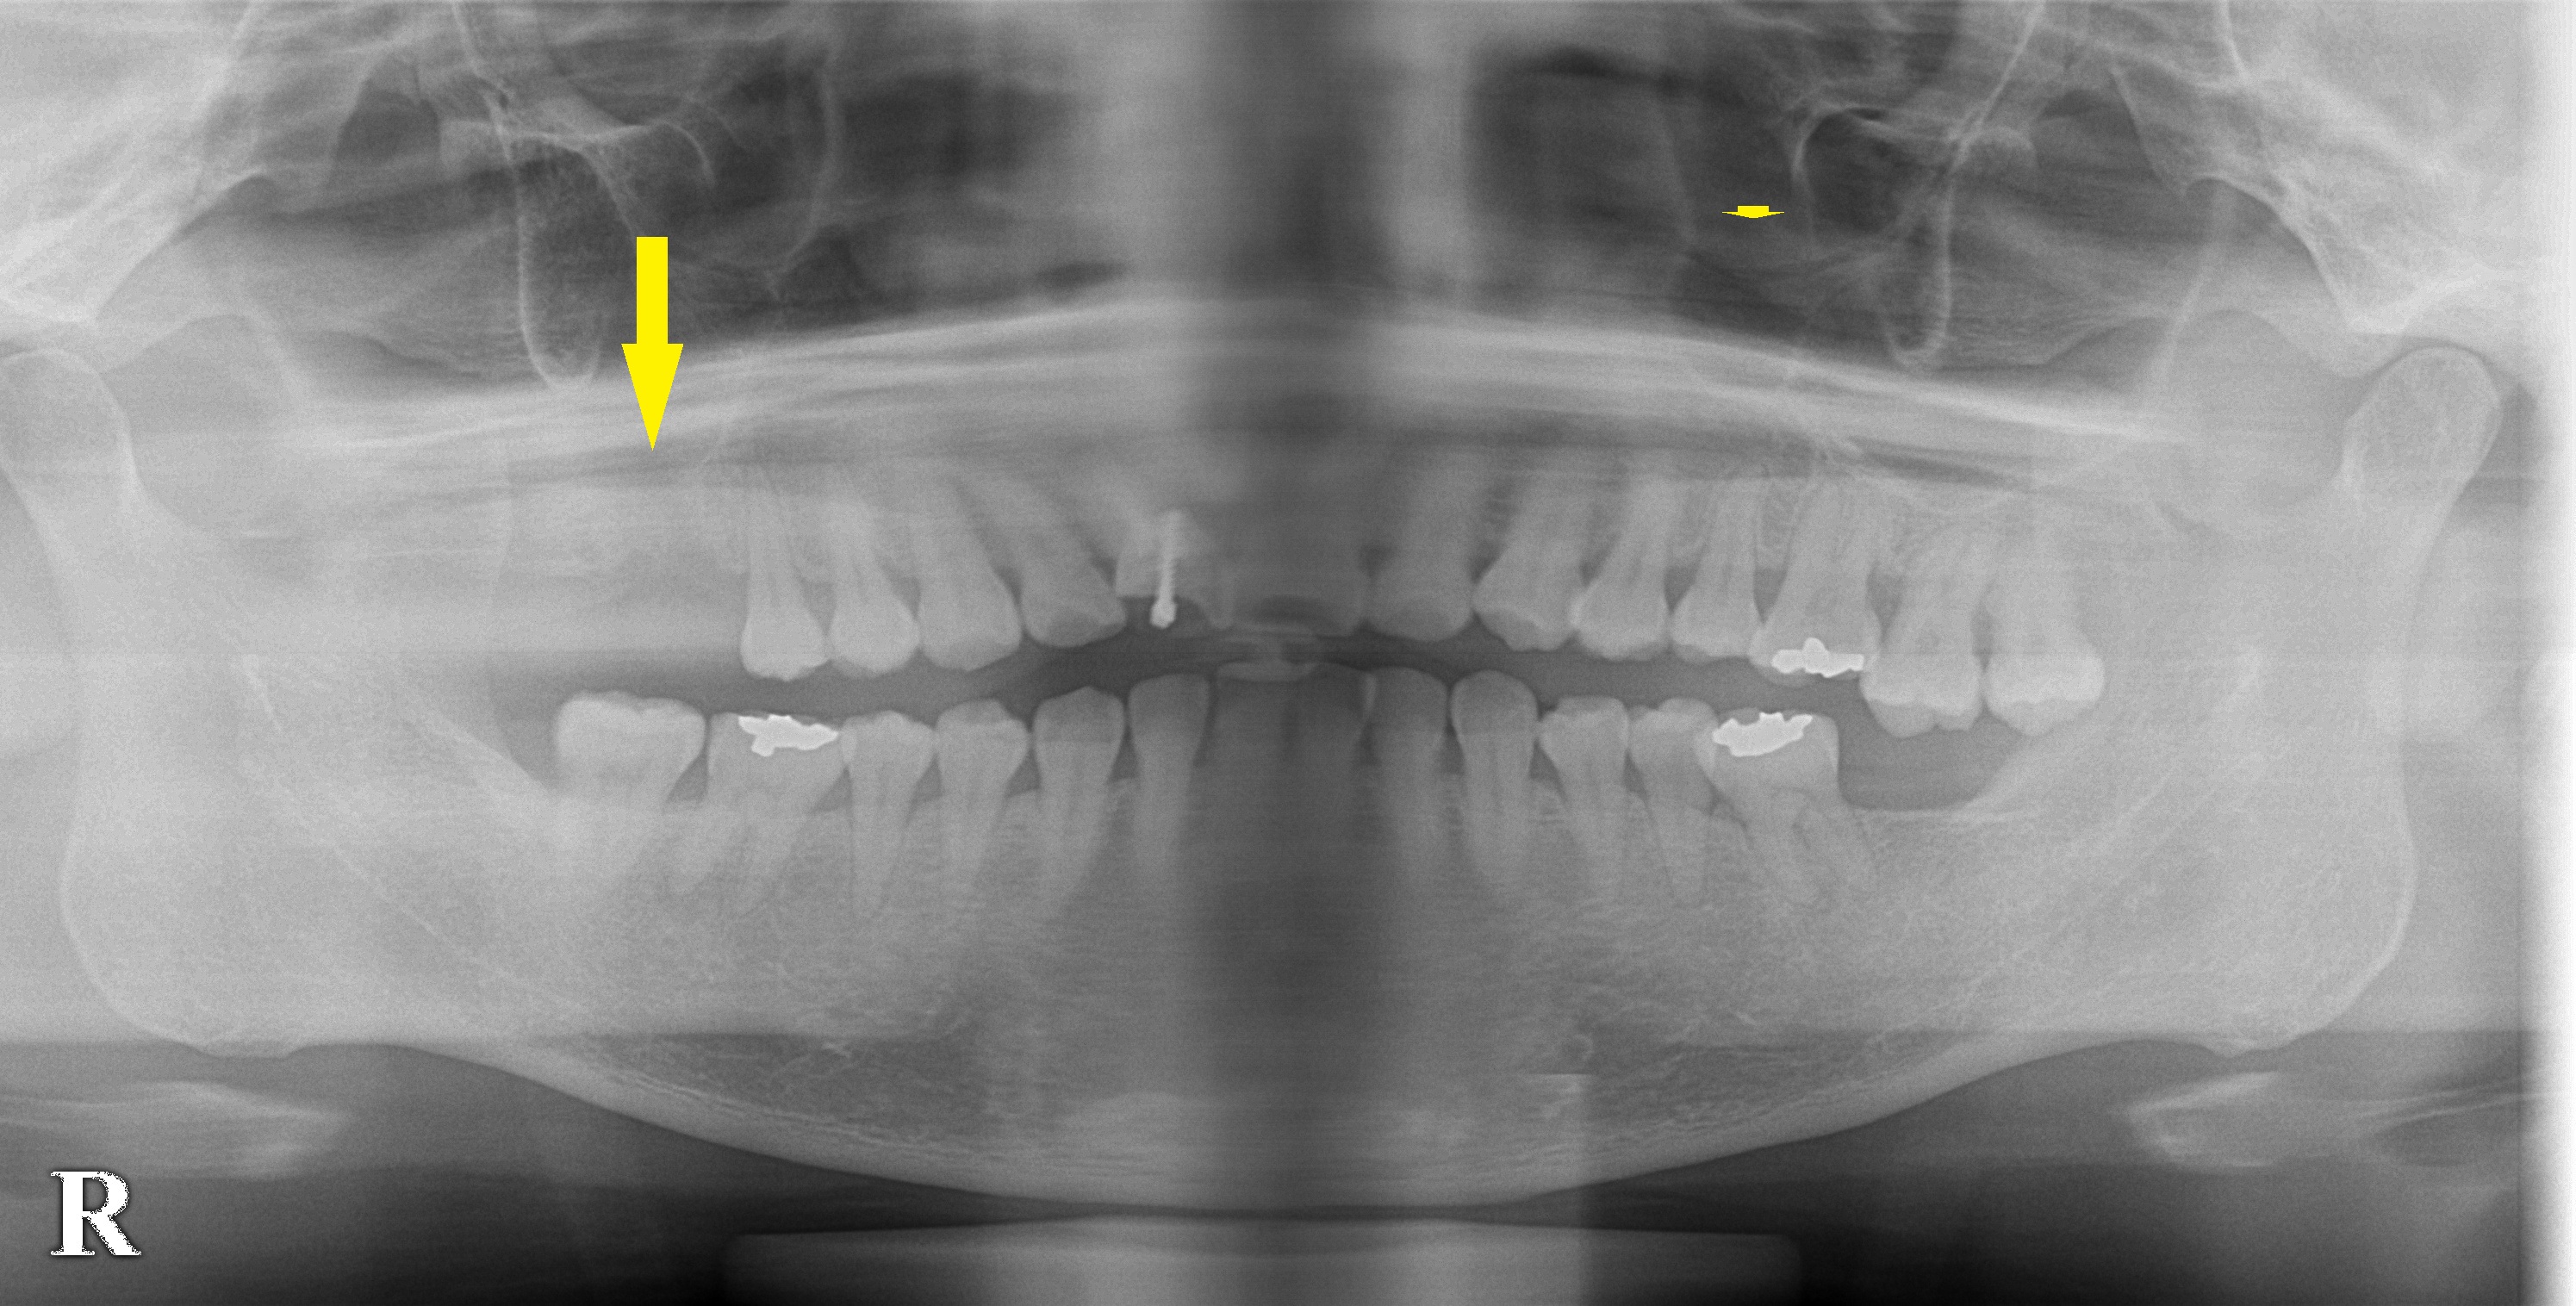

レントゲン写真とCTを撮影してみると、やや骨が薄いことが判明しましたので、ここはソケットリフトという骨造成術を併用して、

インプラント埋入を行う必要があると、説明させていただきました。

下段左の写真が手術前のCT、右が手術後のCTです。